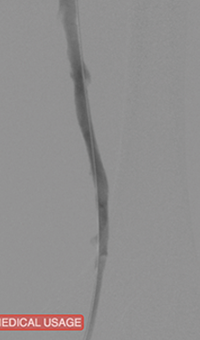

xray image of Iliac vein post-ZelanteDVT.

Iliac vein post-ZelanteDVT

xray image of liac vein post-PTA & stent.

Iliac vein post-PTA & stent

Femoral vein post-ZelanteDVT.

Femoral vein post-ZelanteDVT

Images courtesy of Jeffrey Y. Wang, MD FACS, Vascular Surgeon; Horizon Vascular Specialist, Maryland.  November, 2015